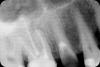

Verba Опубликовано 25 мая, 2009 Поделиться Опубликовано 25 мая, 2009 Доброго времени суток, уважаемые доктора! Требуется квалифицированная консультация! Зуб 5 справа сверху. Ортопедом предложено удаление. Предыстория: за верхушками 6-ки были гранулемы, проведена перепломбировка каналов (в 20-х числах апреля этого года). 5-ка была с анкерным штифтом, коронка была восстановлена композитным материалом (лет 10 назад). Т.К. результат восстановления 6-ки после воспаления никем не гарантируется, доктор решил перепломбировать канал 5-ки, т.к. у нее был вторичный кариес, и удалить анкер с последующей заменой на вкладку и подготовкой зуба под коронку. В результате штифт был удален, но откололся кусок стенки под десной. Канал до конца пройти не удалось, там все зацементировалось накрепко. От 5-ки сейчас осталась тонкая стенка со стороны щеки. Есть ли шанс сохранить этот зуб? Ссылка на комментарий